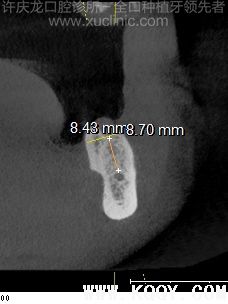

患者,女,2012年6月初诊,时年53岁。全身状况良好。因牙周病拔出大部分牙齿一个月。上下颌后牙区骨量不足,骨质不佳(图1、2、3、4、5、6)。前牙区骨质骨量佳。(图7、8、9、10、11、12、13、14)

| 图7.15位点倾斜测量 | 图8.25位点倾斜测量 | 图9.11位点 | 图10.21位点 |

| 图11.45位点倾斜测量 | 图12.35位点倾斜测量 | 图13.42位点 | 图14.32位点 |

| 图48.15术后六个月 | 图49.11、21术后六个月 | 图50.25术后六个月 |

![]() |

| 图51.45术后六个月 | 图52.42、32术后六个月 | 图53.35术后六个月 |